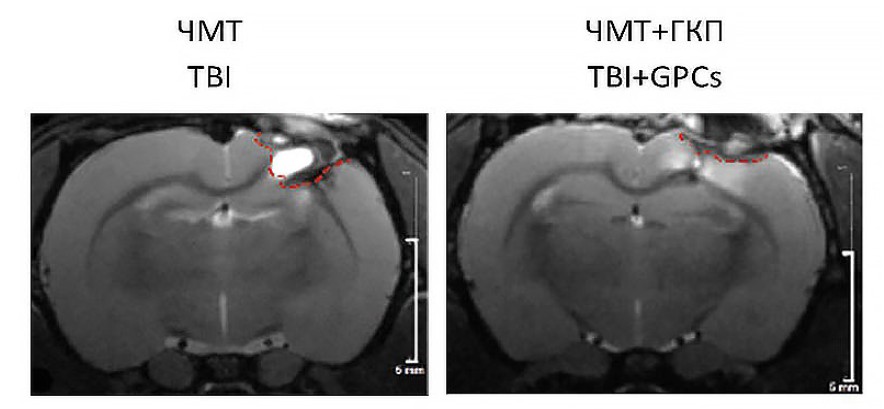

ЧМТ приводила к обширным повреждениям мозга в области сенсомоторной коры (рис. 1.). Для оценки объема повреждения проводили МРТ исследование на 14 сутки после моделирования. Клеточная терапия приводила к снижению объема повреждения в 1,5 раза (таблица 1).

Рис. 1. Репрезентативные МРТ-изображения объема повреждения при моделировании ЧМТ на 14 сутки эксперимента

Примечание: Красной пунктирной линией обозначена зона повреждения. ЧМТ —группа контроля, ЧМТ+ГКП — терапевтическая группа. Масштабная линейка: 5 мм.

Fig.1. Representative MRI images of the damage volume during modeling of TBI on the 14th day of the experiment. The red dotted line indicates the damaged area

Note: TBI is the control group, TBI+GPCs is the therapeutic group. Scale bar: 5 mm.